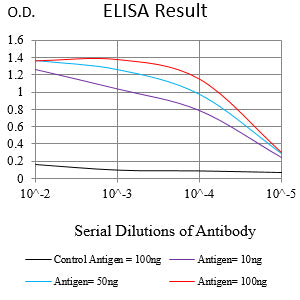

分类: 科研抗体货号: 32437别名: DRCC1; MUC-13应用: WB,IHC,FCM反应种属: Human, Mouse